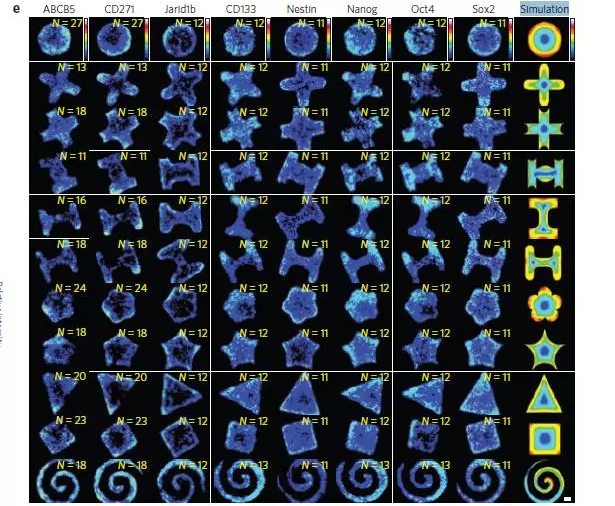

иҷҪ然CSCзҺ°еңЁеҸӘжҳҜдёҖдёӘеҒҮиҜҙ����пјҢеҸҜжҳҜиӮҝзҳӨеӯҰз•ҢеҜ№е…¶и®ӨеҸҜеәҰеҫҲжҳҜй«ҳ���гҖӮдәҺжҳҜзҫҺеӣҪдјҠеҲ©иҜәдјҠе·һеӨ§еӯҰзҡ„з ”з©¶еӣўйҳҹеңЁжғійӮЈдәӣеғҸCSCзҡ„иӮҝзҳӨз»Ҷиғһдјҡжј«иЎҚеңЁиӮҝзҳӨзҡ„д»Җд№ҲйғЁдҪҚ��пјҹдәҺжҳҜ他们жҸҗеҸ–дәҶе°Ҹйј зҺ„иүІзҙ зҳӨз»Ҷиғһ����пјҢе°Ҷе…¶ж”ҫеңЁз”ЁдёҖз§Қж°ҙеҮқиғ¶дҝ®е»әзҡ„2Dе’Ң3DдҪңиӮІжғ…еҪўдёӯ���гҖӮз”ұдәҺйҖҡиҝҮиҪҜе…үеҲ»жүӢиүәе°Ҷе·®еҲ«еј№жҖ§зҡ„ж°ҙеҮқиғ¶дёӯзҡ„е…ұиҪӯеҹәиҙЁеҚөзҷҪеұӮеј„жҲҗзү№е®ҡзҡ„еҮ дҪ•еӣҫеҪў����пјҢеҘҪжҜ”дә”и§’жҳҹгҖҒе°ҸиҠұгҖҒеҚҒеӯ—еҪўзӯүзӯү����пјҢжүҖдҪңиӮІзҡ„иӮҝзҳӨз»„з»Үе°ұдјҡжҲҗдёәзү№е®ҡзҡ„еҪўзҠ¶���гҖӮ

еңЁеҲ’еҲҶдҪңиӮІдәҶ1гҖҒ3гҖҒ5еӨ©еҗҺ����пјҢз ”з©¶иҒҢе‘ҳдёҲйҮҸиў«и®Өе®ҡжҳҜCSCзҡ„ж Үи®°зү©пјҲеҘҪжҜ”д№ӢеүҚжүҖиҜҙзҡ„CD133гҖҒSox2гҖҒCD271зӯүзӯүпјү����пјҢж•ҲжһңжңүзӮ№и®©дәәж„ҸеӨ–���гҖӮ

дёҺжӯЈеёёе№Із»Ҷиғһе–ңж¬ўжё©жҡ–ж№ҝж¶Ұзҡ„дёӯеҝғдҪҚзҪ®е·®еҲ«����пјҢзҺ„иүІзҙ зҳӨCSCж ·з»ҶиғһзңӢиө·жқҘе–ңж¬ўиҫ№иҫ№и§’и§’гҖҒй«ҳдҪҺдёҚе№ізҡ„ең°ж–№����пјҢе…¶д»–зҷҢз—ҮжҳҜеҗҰд№ҹжҳҜиҝҷж ·��пјҹдәҺжҳҜ他们еҸҲз”ЁдәҶиӮәзҷҢз»ҶиғһпјҲA549пјүгҖҒеүҚзәҝи…әзҷҢз»ҶиғһпјҲPC3пјү����пјҢз”ҡиҮіжҳҜи‘—еҗҚзҡ„жө·жӢүз»Ҷиғһзі»����пјҢж•ҲжһңйғҪжҳҜзӣёиҝ‘зҡ„���гҖӮдёҚдҪҶдә‘дә‘����пјҢиһәж—ӢеҪўдҪңиӮІзҡ„CSCж ·з»ҶиғһйҳіжҖ§зҺҮжңҖй«ҳпјҒд№ҹе°ұжҳҜиҜҙ����пјҢиӮҝзҳӨз»„з»Үзҡ„еҪўзҠ¶и¶ҠжүӯжӣІ����пјҢCSCйҳіжҖ§зҺҮи¶Ҡй«ҳ����пјҢиӮҝзҳӨиҪ¬з§»зҡ„еҚұе®іи¶Ҡй«ҳпјҒ